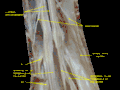

- Spinal cord. Spinal membranes and nerve roots.Deep dissection. Posterior view.

Spinal cord. Spinal membranes and nerve roots.Deep dissection. Posterior view.